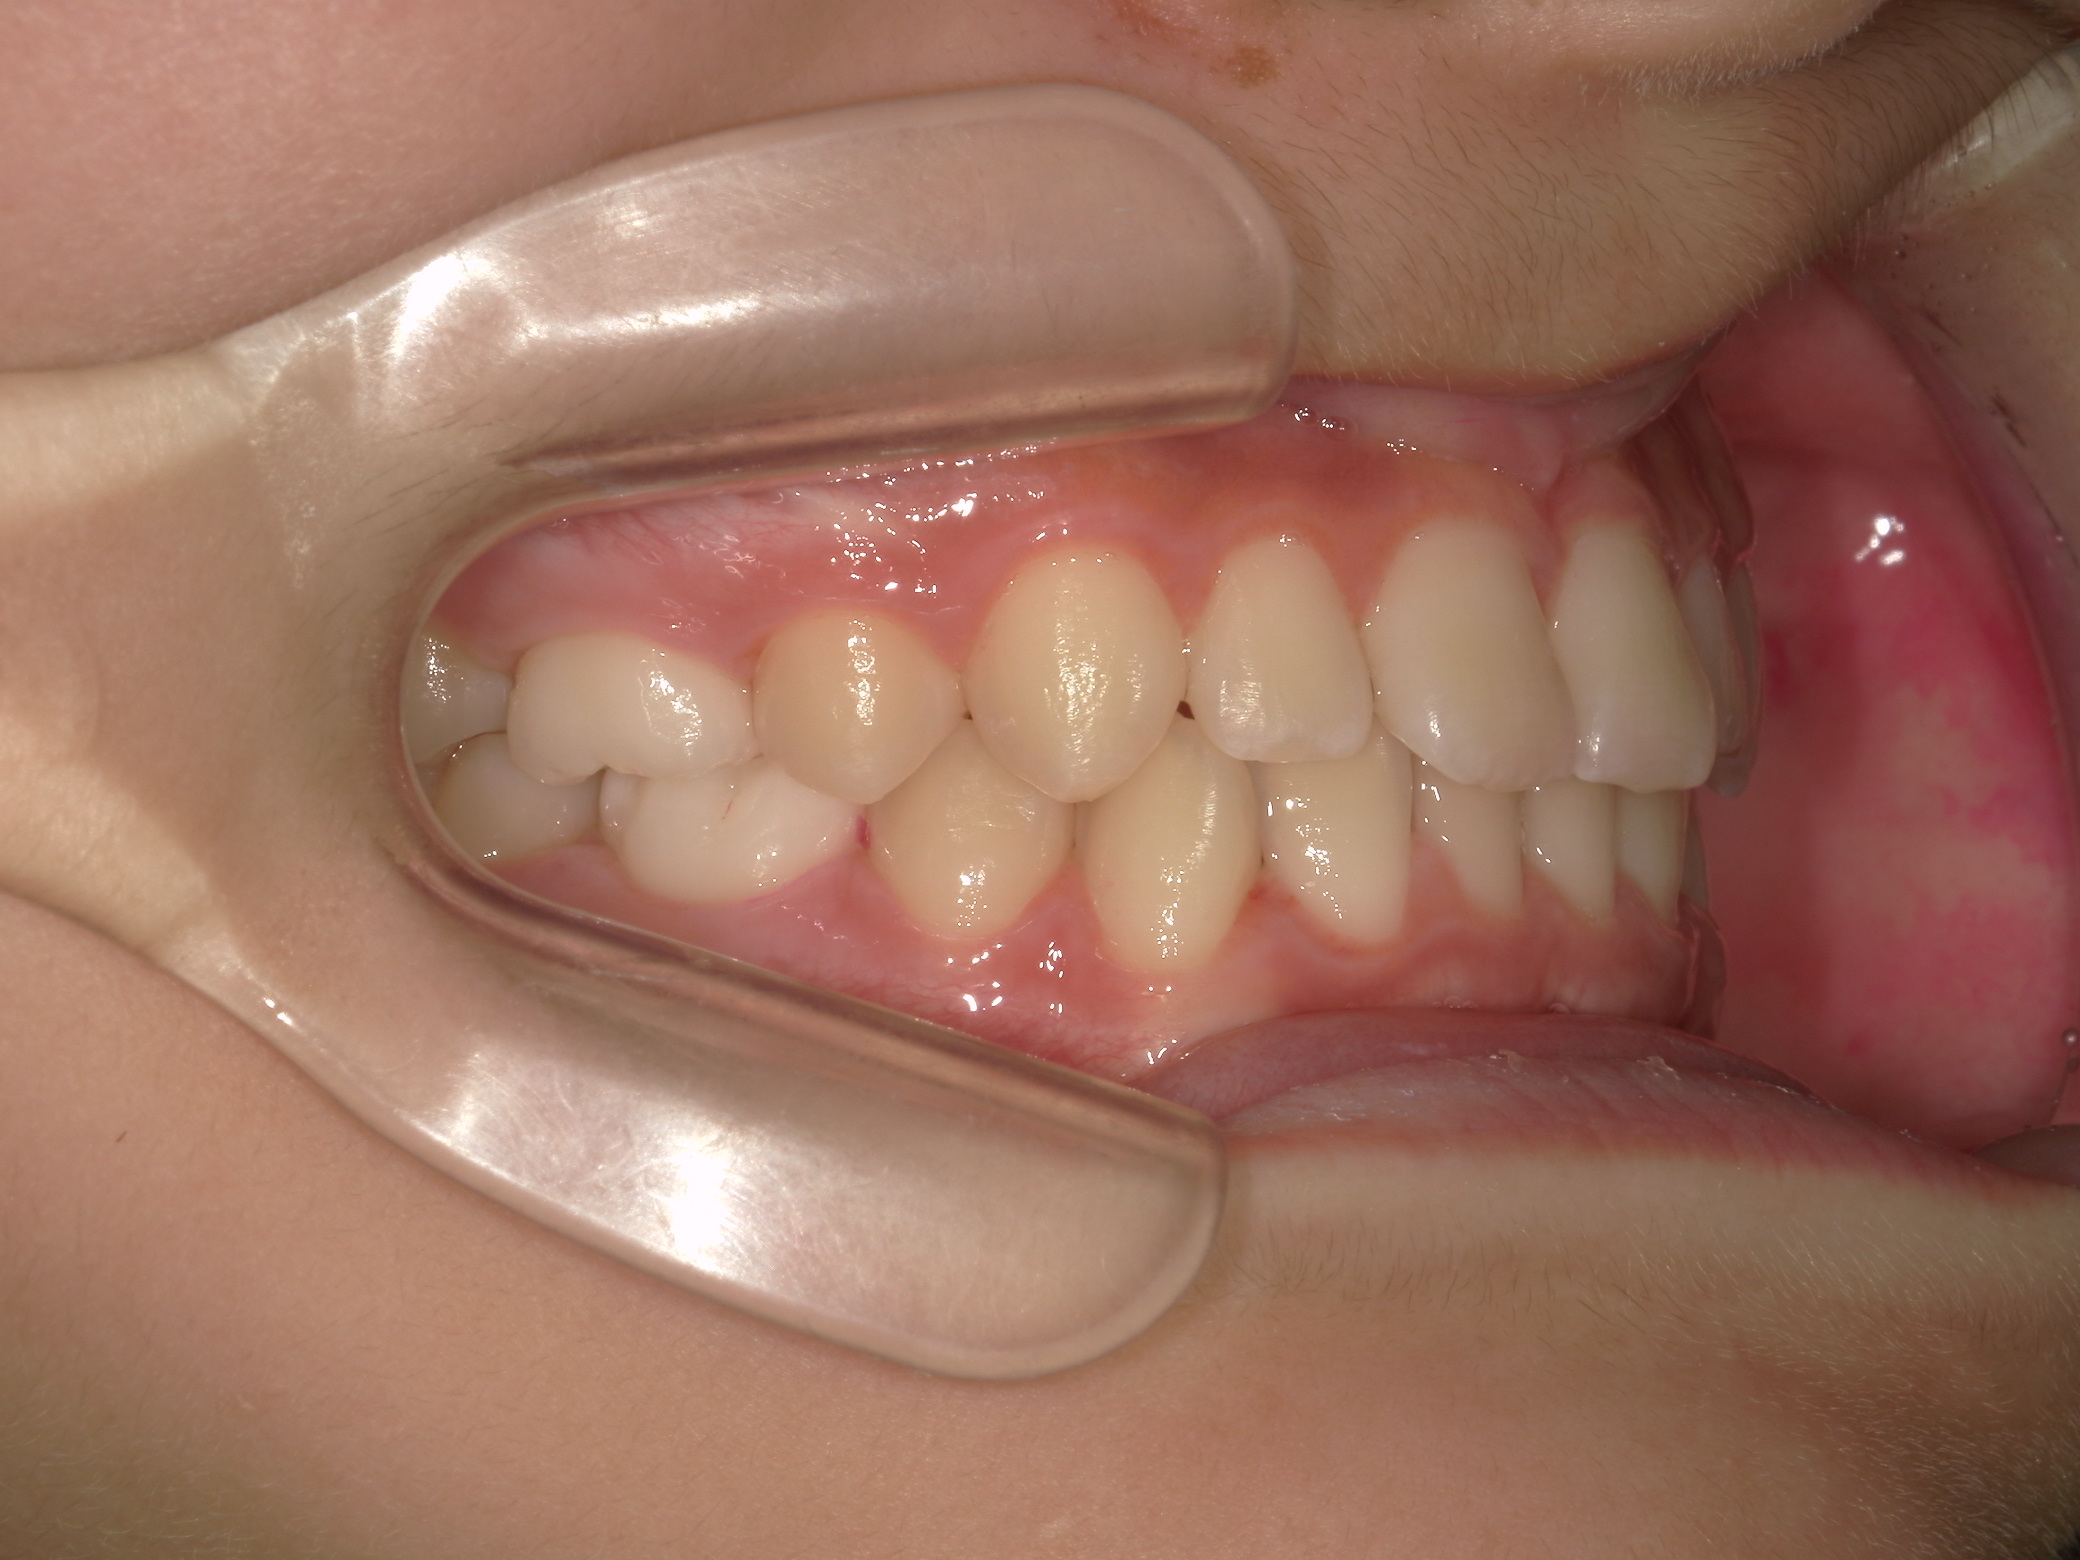

【小学生】マイオブレース矯正 反対咬合を改善

小学生で開始

マイオブレース

受け口

非抜歯

1期治療のみで改善

Before

After

治療期間

1.6年

治療開始

8歳

種類

マイオブレース矯正

使用装置

機能矯正装置

コメント

治療にしっかり取り組んでくれたのでスムーズに治りました。

治療後3年経過した今でも 装置もいれずに 後戻りもしていません。